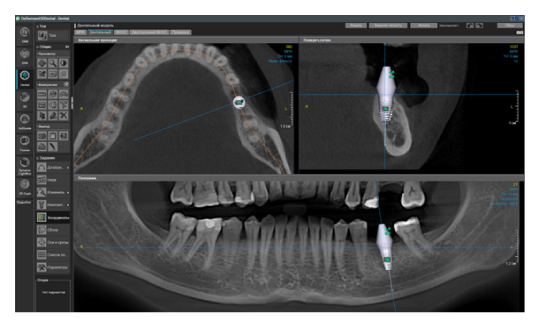

Подводя итог, чем больше конусно-лучевой компьютерный томограф может выдать вариантов FOV – тем больше разных кейсов вы для себя закроете с точки зрения комфортной диагностики. Ниже пример моего подхода в назначениях зоны сканирования.

Рис. 1. Представлены два исследования (10x10 см и 20x20 см). На обоих изображениях хорошо видна канально-корневая система зубов, но, если масштабировать второе исследование, то качество неминуемо снизится, как и диагностическая эндодонтическая эффективность.